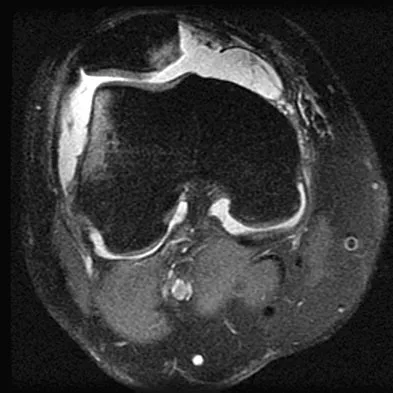

A 14-year-old patient has anterior knee pain. Radiographs, an MRI scan, and biopsy specimens are shown in Figures 6a through 6e. What is the most likely diagnosis?

Explanation:

Although the imaging studies are consistent with a unicameral bone cyst, aneurysmal bone cyst, or giant cell tumor, the histology shows small round blue cells that are typical of Ewing's sarcoma. Although Ewing's sarcoma frequently occurs in the diaphysis, it can occur in the metaphysis.